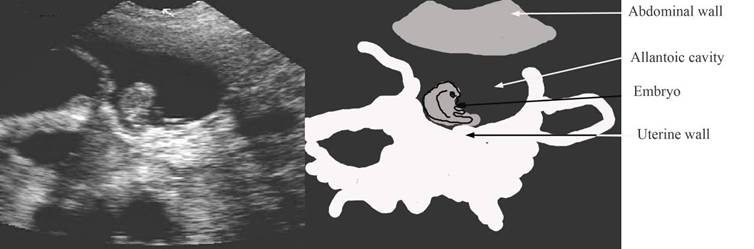

35 days – note the uterine vesicles easy to see with prominent embryo

repro draw 30 days gestation pics label.jpg